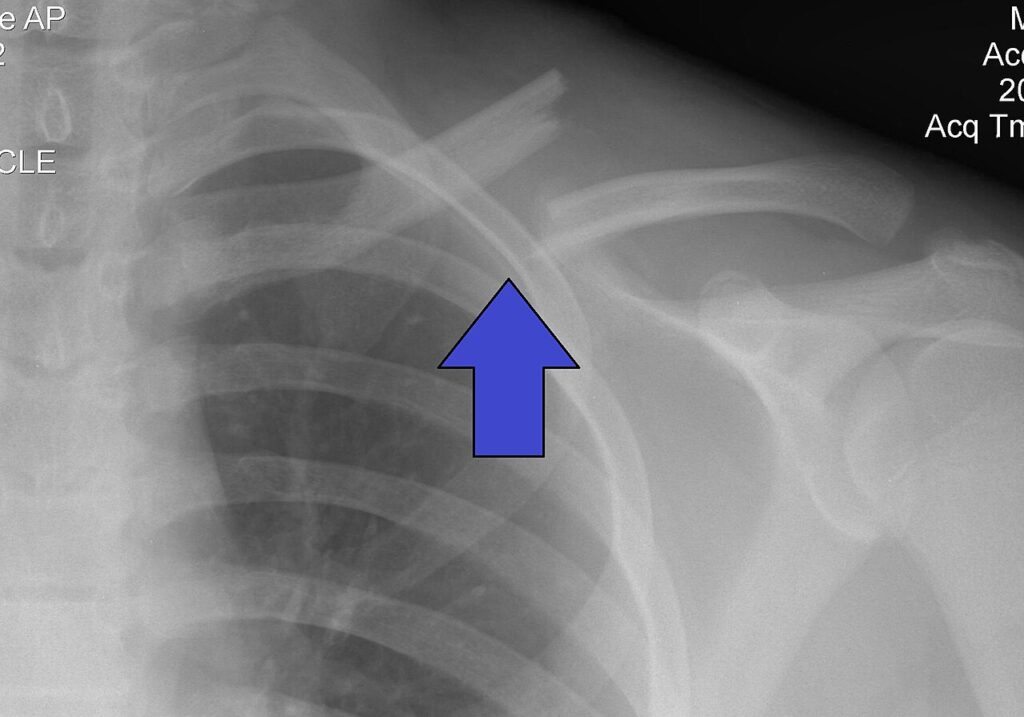

| X-ray of a left clavicle fracture | |

If a clavicle fracture is suspected, the initial method to evaluate for a clavicle fracture is by an AP (anterioposterior) or PA (posterioanterior) X-ray of the affected clavicle to determine the fracture type and extent of injury.[5][6] When an AP or PA view of the clavicle is taken, the xray beam is horizontal versus the body and the first rib and other structures overlap the clavicle which can make it more difficult to assess the clavicle, to avoid the overlap of other structures an xray of the clavicle can be obtained with a 20-30 degree cephalad (toward the head) to isolate the clavicle.[5][6] Although the degree of shortening of the clavicle can be often be assessed from the AP or PA dedicated clavicle images, additional AP or PA views of the chest can be taken to compare both clavicles for length or evaluate for other injuries that may be present such as rib fractures.[5][6] In cases where the physician suspects the fracture may involve the joint surfaces of the clavicle, to differentiate an epiphyseal injury from a sternoclavicular (SC) joint dislocation, or to evaluate injury to underlying neurovascular structures they may order a computerized tomography (CT) scan.[5][6] Diagnosis through ultrasound imaging performed in the emergency room may be utilized in children.[10]